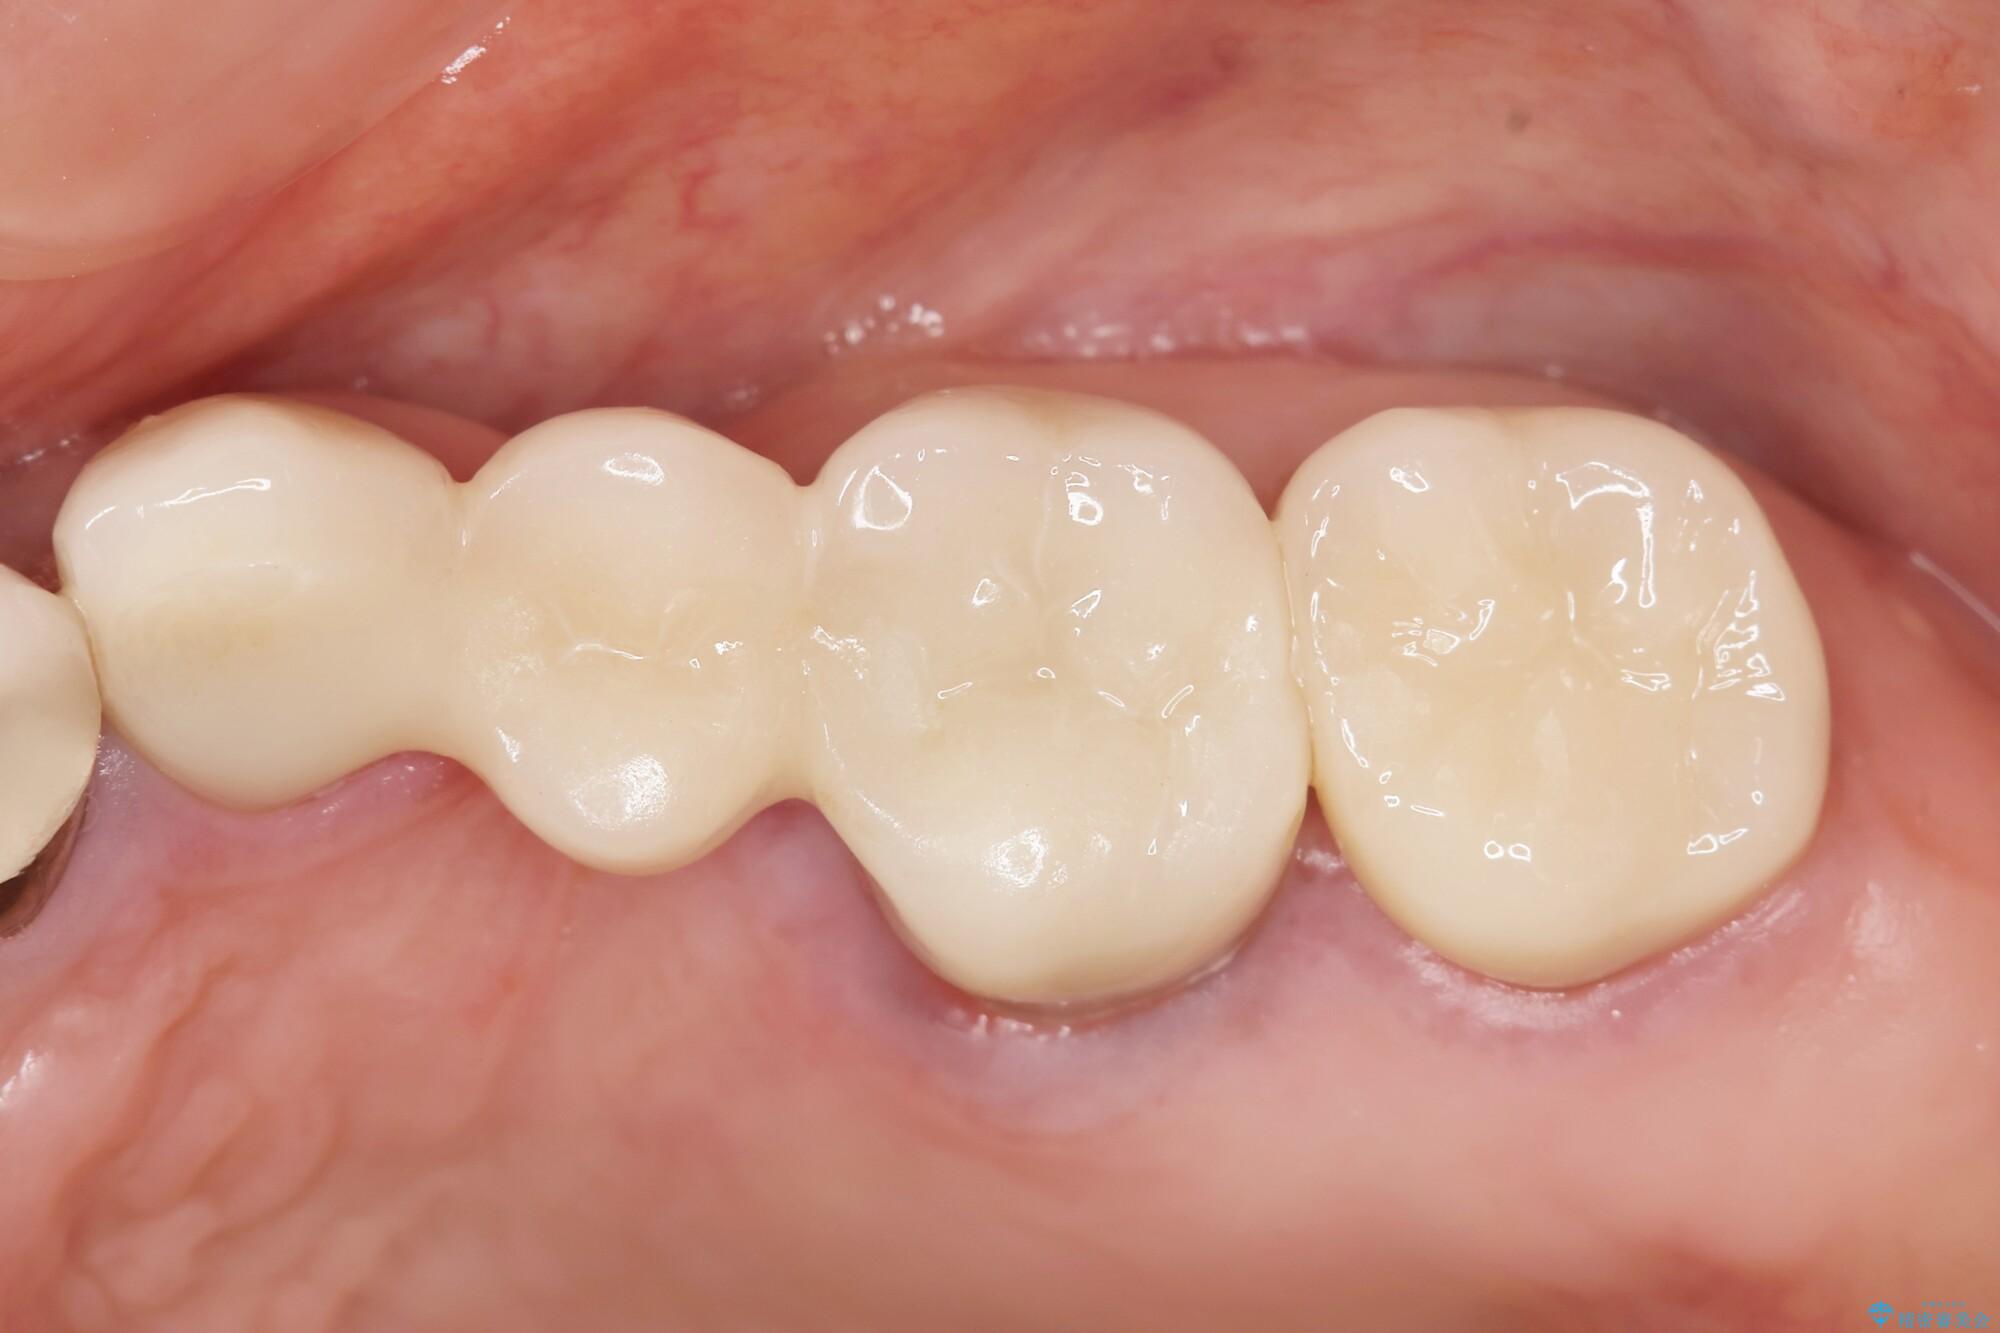

まず検査を行い、歯周病や歯内の問題がないことを確認しました。

銀歯をジルコニアセラミックへと換えることで、審美性・清掃性の高い仕上がりを目指します。

治療後について

ブリッジに審美的でないイメージやあまり良くないイメージをお持ちの方を多々お見受けしますが、適切な設計とすることで、見た目に自然で審美的なブリッジ治療を行うことができます。